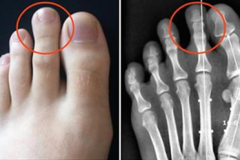

Это гены: Наталья Орейро показала молодую красавицу-маму Создана первая в мире говорящая сексуальная кукла (Видео) Гороскоп красоты: особенности внешности разных знаков зодиака Вот что КАТЕГОРИЧЕСКИ нельзя делать в чистый четверг Этот ребенок умер ещё во чреве матери. Однако то, что произошло дальше — самое н... Внебрачная дочь Джеки Чана попыталась покончить с собой 13 скрытых признаков того, что вы не так здоровы, как вам кажется Считается, что самый смертоносный напиток в мире, он может убивать вас менее чем... Какой вы цветок по знаку Зодиака Ксения Бородина впервые показала нос после возможной ринопластики (Фото) Если доску для утюга накрыть фольгой, гладить можно в 2 раза быстрее! Вот почему Дочь Майкла Джексона отметила 19-летие, поедая бургеры на обочине (фото) Ей пришлось отдать ребенка,которого она считала своим- ужас! В роддоме 25 лет на... Как понять, что он тебя любит: 10 верных признаков Что будет, если три года совсем не подстригать ногти (Фото) Указательный палец длиннее других? Вот что это может сказать о Вашем характере В армии Таиланда начался весенний призыв Не виновата она! Хлое Севиньи случайно показала лишнее в очень короткой юбке (Ф... 10 видов женщин, от которых всегда сбегают мужчины Будь стильной этим летом: 8 основных модных тенденций 2017 года Ожидания и реальность: фанатка Кейт Миддлтон копирует все образы герцогини Что на этой картинке кажется вам наиболее странным? Мой ласковый и нежный зверь: знаменитости, которые встречались с мужчинами-тиранами ОПРЕДЕЛЯЕМ ИМИДЖ ПО ЗНАКУ ЗОДИАКА Она родила близнецов. Но один из них на 2 года старше второго Принимайте этот мощный сироп, чтобы растворить камни в почках Весь персонал больницы пребывал в шоке, узнав, что бабушка хотела сделать с внуком ВРЕМЯ ДЛЯ ПРЕДСКАЗАНИЙ: ВЫБЕРИТЕ ФРУКТ И УЗНАЙТЕ СВОЕ БУДУЩЕЕ Как вы думаете, кто из этих малышей — девочка? Мать намазала 3-месячного малыша солнцезащитным кремом! И вот что с ним стало